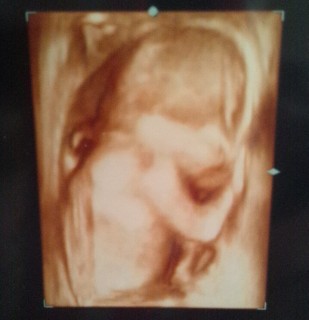

パパと一緒にエコーを見ました。可愛い成長に感動の連続でした!まだ胎動はないけれど、こんなに元気に動いているなんて(*^^*)ずっと見ていたかったです♪

指しゃぶりかな!?

可愛くてずっとみていたかったです!

両手で目もとをおおっているところでした。右手のゆびが赤ちゃんらしくて、感激してしまいました。